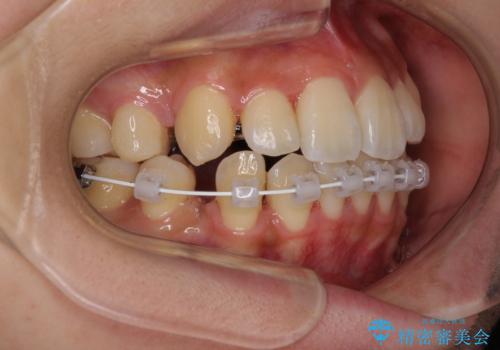

- ハーフリンガル

- 前歯のデコボコやクロスバイトと上顎の前突感による口の閉じにくさを気にして来院された患者様です。

目立たない装置を希望されたので、上顎が裏側装置のハーフリンガルを選択し、上下左右の小臼歯(計4歯)を抜歯して矯正治療を行うこととしました。